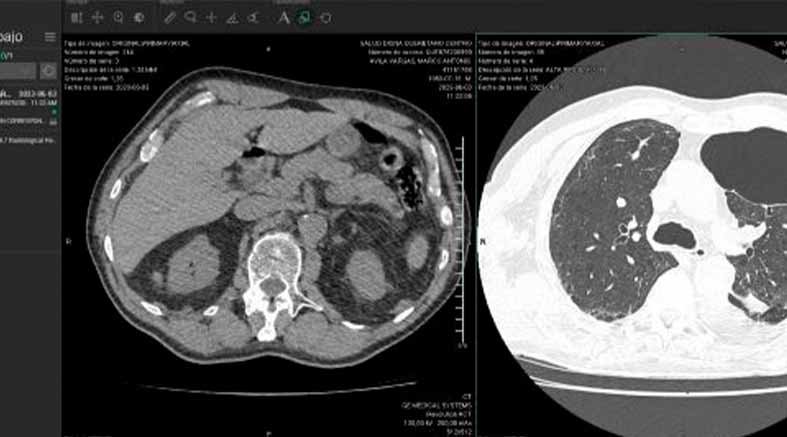

También requirió de una traqueostomía y una gastrostomía. Algunas infecciones hospitalarias agravaron su salud pero la Fe siempre estuvo presente y al fin, logró salir del hospital. En casa iniciamos otra etapa. Inhaloterapia, Fisioterapia, Nutrióloga y Terapia de deglución, todo para poder lograr su recuperación. Su gran esfuerzo y el apoyo de su familia han dado resultados. Ha mejorado mucho y va por buen camino pero aún falta trecho por recorrer. Hace un par de meses, en una tomografía de control se le descubrió una bulla de gran tamaño en el pulmón izquierdo. El tratamiento es quirúrgico y de no hacerse la cirugía, la salud de Marco está en riesgo y con graves consecuencias. Por eso necesita operarse.